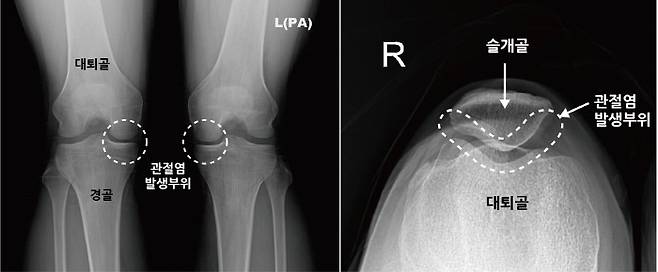

우리가 일반적으로 알고 있는 무릎 관절염(퇴행성 관절염)은 대퇴골과 경골 사이에 있는 연골 손상으로 관절염이 진행될수록 무릎의 관절 간격이 좁아지기 때문에 심한 경우, X-레이만으로도 비교적 쉽게 진단이 가능하다. 하지만 슬개대퇴관절염은 질환이 어느 정도 진행된 경우에도 X-레이 검사상 이상 소견을 발견하기 어렵기 때문에 진단이 쉽지 않다. 그래서 종종 진단과 치료 시기를 놓치게 되어 증상이 악화되기도 한다.